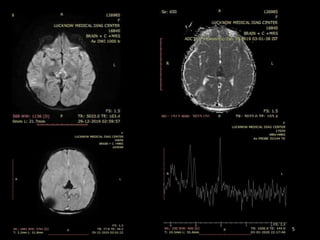

IMAGING FINDINGS

CT FINDINGS

• NECT-

Hyper dense compared to brain .

Appear to be “draped” around the posterior third ventricle.

Obstructive hydrocephalus is variable.

Pineal calcifications are “engulfed” and surrounded by tumor .

Look for a second lesion in the suprasellar region!

• CECT- Strong uniform enhancement is typical.

MR FINDINGS

• Iso- to slightly hyperintense to cortex on T1- and T2WI.

• T2* (GRE, SWI) may show “blooming” due to intratumoral

calcification.

• Enhancement is strong and usually homogeneous .

• Because of their high cellularity, germinomas may show

restricted diffusion.

CASE SUMMARY

• 9yr old female patient present with headache and

numbness of limbs

• On imaging shows Relatively well define

hetrogenous enhancing mass lesion in pineal region

and concurrent suprasellar mass with

leptomeningeal spread

• Likely Diagnosis is GERMINOMA

• HPE is awaited